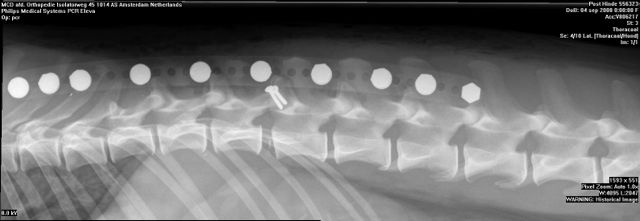

Hinde’s nacontrole in Amsterdam 08 zaterdag nov 2014 Originele grootte op 640 × 221 ≈ Een reactie plaatsen